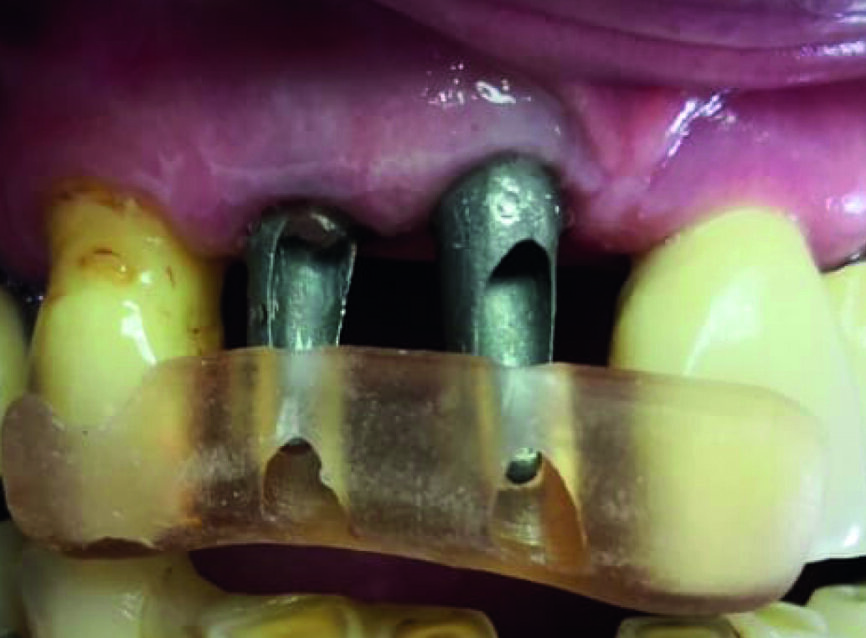

Figs. 6a et b : Réalisation d’un trou en face palatine des couronnes provisoires, permettant le rebasage au fauteuil. Notez la facilité d’insertion des couronnes à travers les piliers provisoires.

L’intervention est programmée en février 2019. Des implants de type Avinent Ocean hexagone interne sont poses. Afin de sécuriser la pose des implants et assurer l’assainissement du site, un lambeau est réalisé après l’extraction des deux dents. Toute la séquence de forage ainsi que la pose des implants sont passés à travers les douilles du guide chirurgical. L’indexation doit être bien respectée en alignant les repères présents sur le guide avec ceux du porte implant.

Les implants sont vissés à la main à l’aide d’une clé dynamométrique. Nous vissons ensuite les piliers temporaires (Avinent), et les couronnes provisoires en résine PMMA sont rebasées et scellées (laboratoire Crown Ceram) avant de suturer le lambeau. À ce stade, notons que le second avantage du lambeau est de pouvoir aussi contrôler parfaitement l’adaptation prothétique, et d’éviter toute fusée de ciment de scellement. Une radio de contrôle postopératoire est réalisée (Fig. 7).